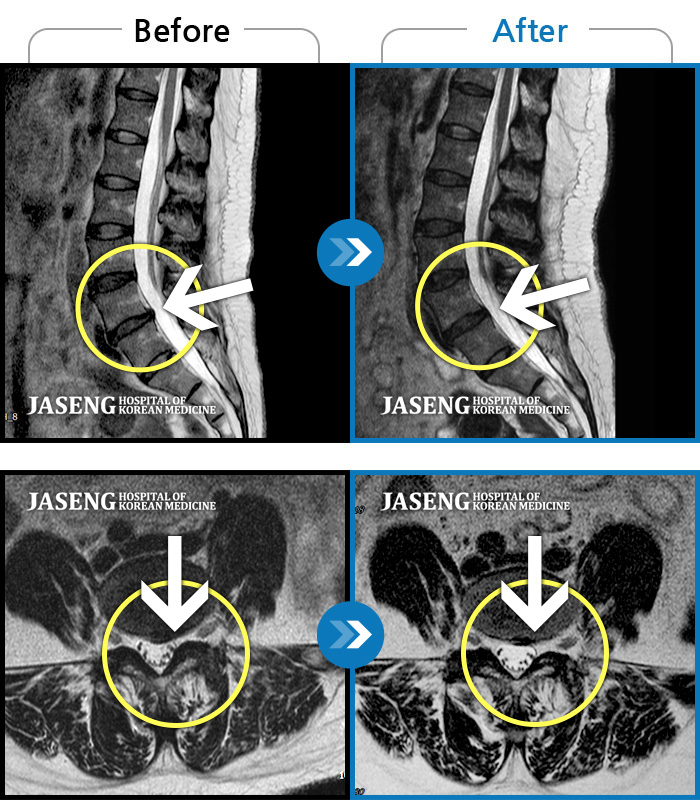

Before

After

환자에게 사전 동의를 받아 동일 조건에서 촬영되었습니다.

개인에 따라 치료 후 부작용이 발생할 수 있으니 의료진과 상담 후 치료를 진행하시기 바랍니다.

2023.12월경에 눈길에 걷다가 삐끗한 후 발생한 허리 통증으로 오신 분입니다.